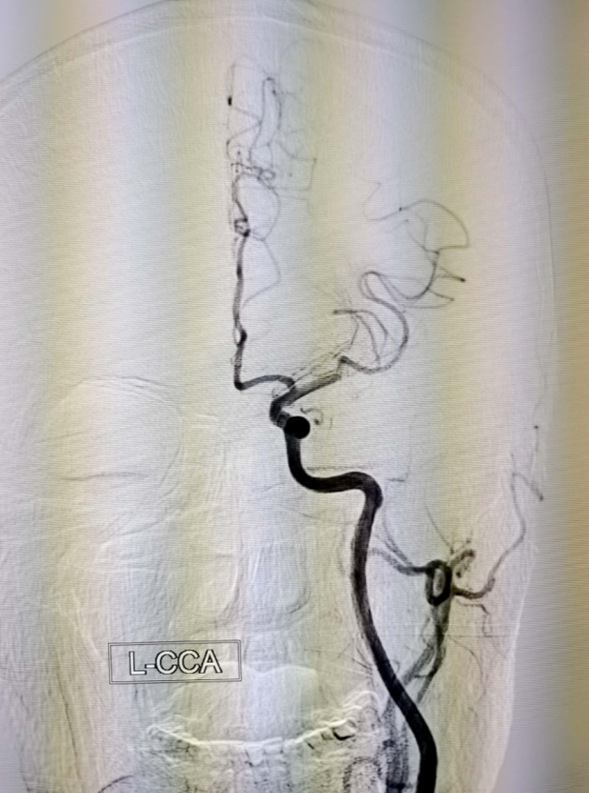

术前左侧颈内动脉正位造影